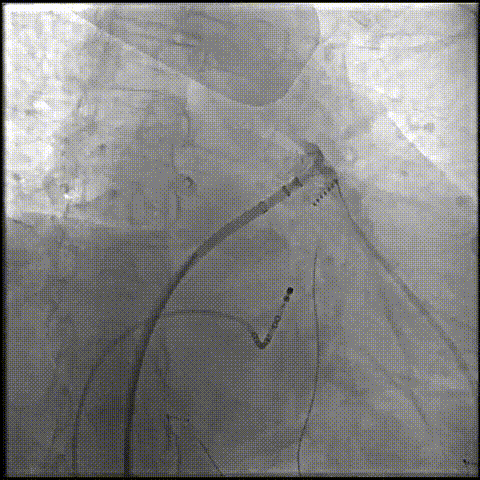

RAO 30° CAUD 20°测量锚定区:20.3mm;封堵区:24.0mm。

RAO 30° CAUD 20°造影

选择LAMax LAAC® 2430 Normal型号左心耳封堵器。

锚定伞锚定在主干区域,再将封堵盘逐渐打开,保证封堵效果,封堵盘完全打开后造影,外盘覆盖外口,封堵完全,无残余分流。

打开封堵盘

打开封堵盘造影

LAMax LAAC® 2430 Normal封堵器封堵盘在DSA下牵拉15s,锚定伞稳定无移位。

牵拉实验